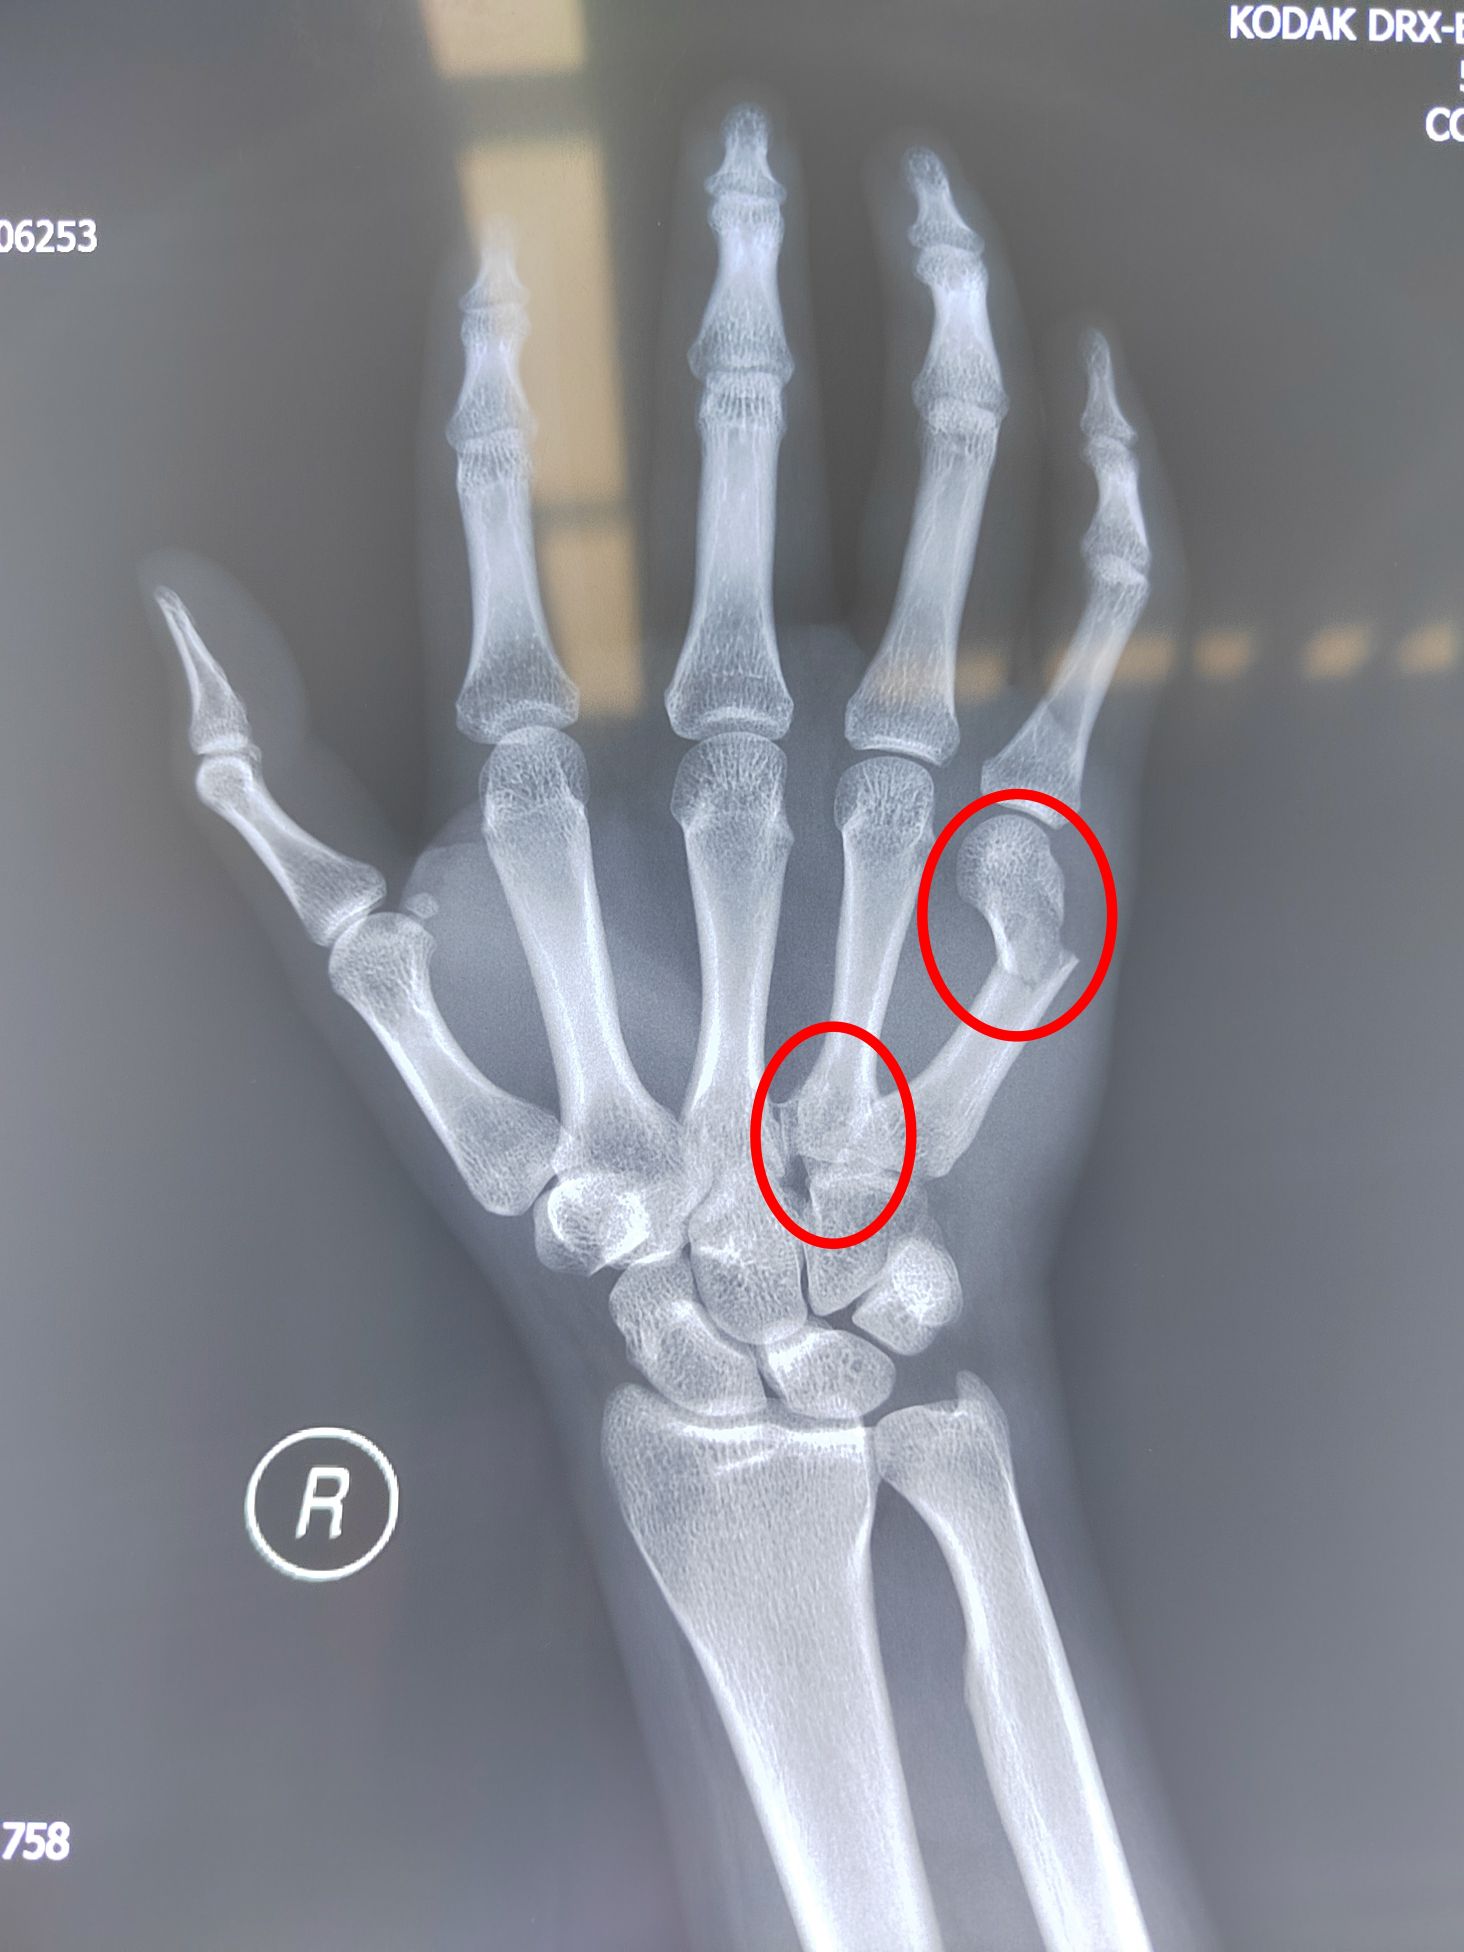

对于每一位高三考生来说,高考是当前最为重要的事情,今年20岁的小马,是孟津区的一名高三考生,2024年6月4日晚上不慎摔伤,导致右手疼痛难忍。到附近医院检查后发现“右手第5掌骨颈骨折,右手第4掌骨基底部骨折”。右手对于一个即将参加高考的高三学生来说,重要性不言而喻,右手骨折后还能不能顺利参加高考成了一个未知数。这场突如其来的意外,使一家人笼罩在阴影之中,焦虑万分。有医生建议放弃考试,先治疗骨折,也有医生建议先忍痛参加考试,考完后再治疗骨折,如何抉择成为摆在家长面前的一道难题。

术前影像检查